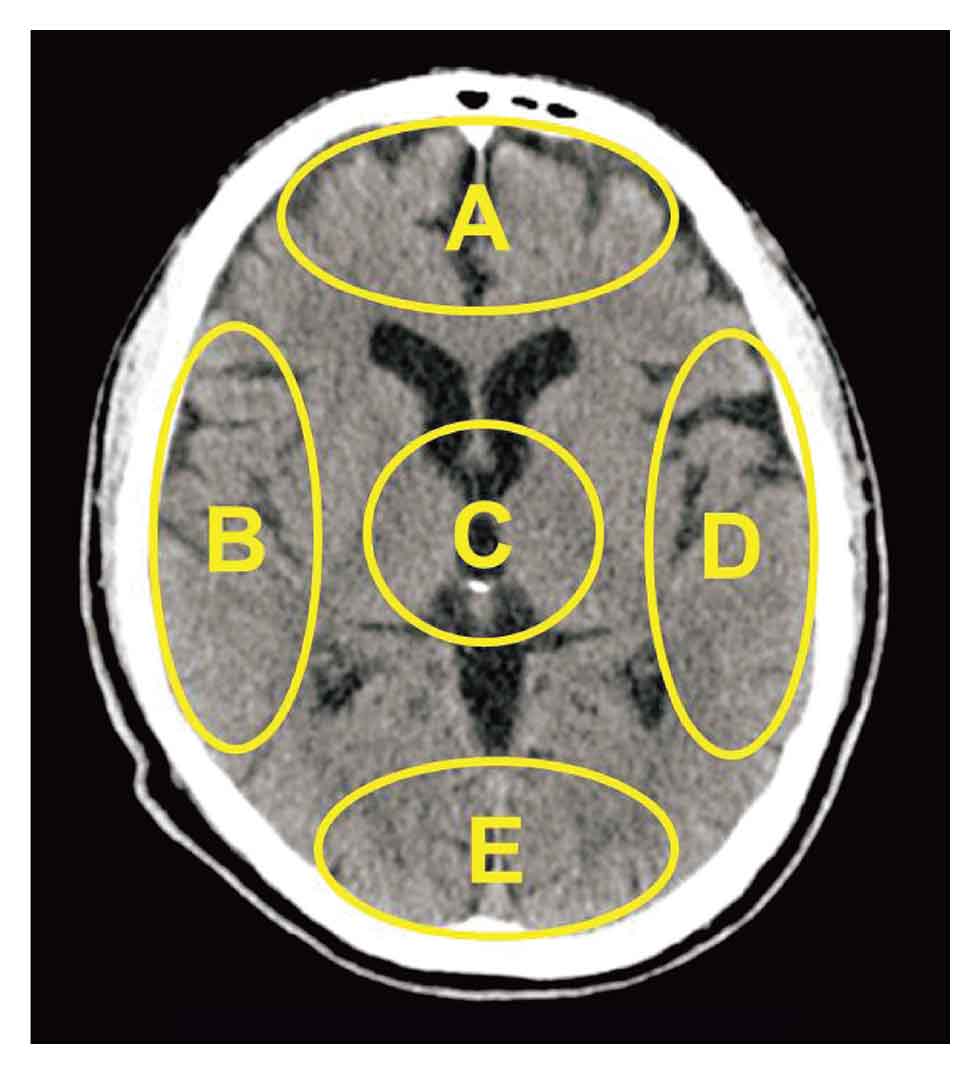

図:脳卒中例のct画像 おわりに 本稿では、脳の基本的解剖・生理、および、ct読影のためのctの基礎知識を中心に解説した。今後、mriと脳血管障害の基礎知識を解説していく予定である。 参考文献 脳の成分 脳には、約140億個もの神経細胞があります。 しかし、これは脳全体で見るとわずか1割程度にしか過ぎず、残りはグリア細胞という神経細胞に栄養を送る役割を持つものです。 かつて、「人間が使う脳は1割くらいで、残りの9割は使うことなく脳トレゲーム・知育アプリ (無料・DL不要) 反射神経ゲーム お題と同じ絵を5回選んで、反射神経を測定しよう☆ 記憶力ゲーム ネコ画像の位置を覚えて記憶力チェック。 レベルは全17段階♪ 瞬間視力ゲーム 一瞬で表示される絵柄を見極めよう。 001秒

頭部ct 脳ct 正常像の各名称 救命救急センター 東京医科大学八王子医療センター